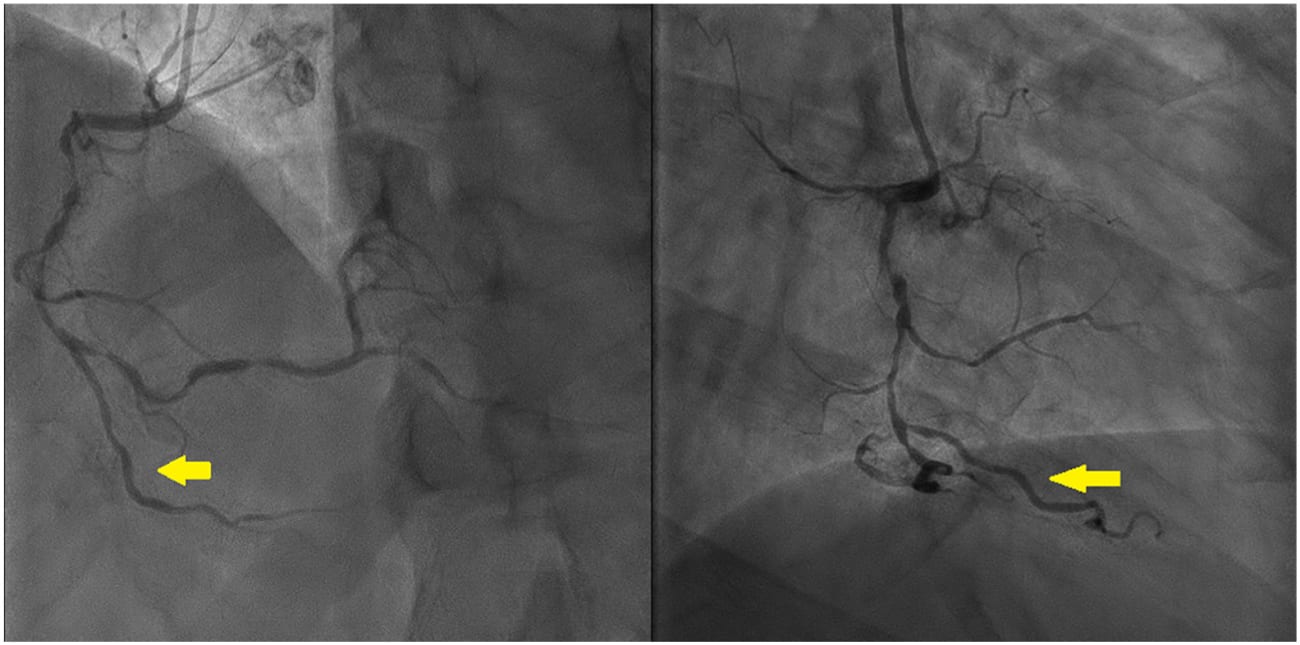

Different angle of the images of the right coronary artery angiogram shows diffuse significant stenosis across acute marginal branch (yellow arrow).